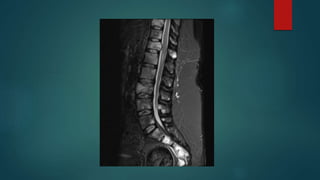

Spinal Cord Compression

Magnetic Resonance Imaging

Pros

 Superior contrast resolution

 Staging purposes

 No ionizing radiation

Cons

 Poor spatial resolution

 Slow

 Costly

 Limited utility in the emergent setting

 Physical Restrictions

 Artifacts

 Patient tolerance